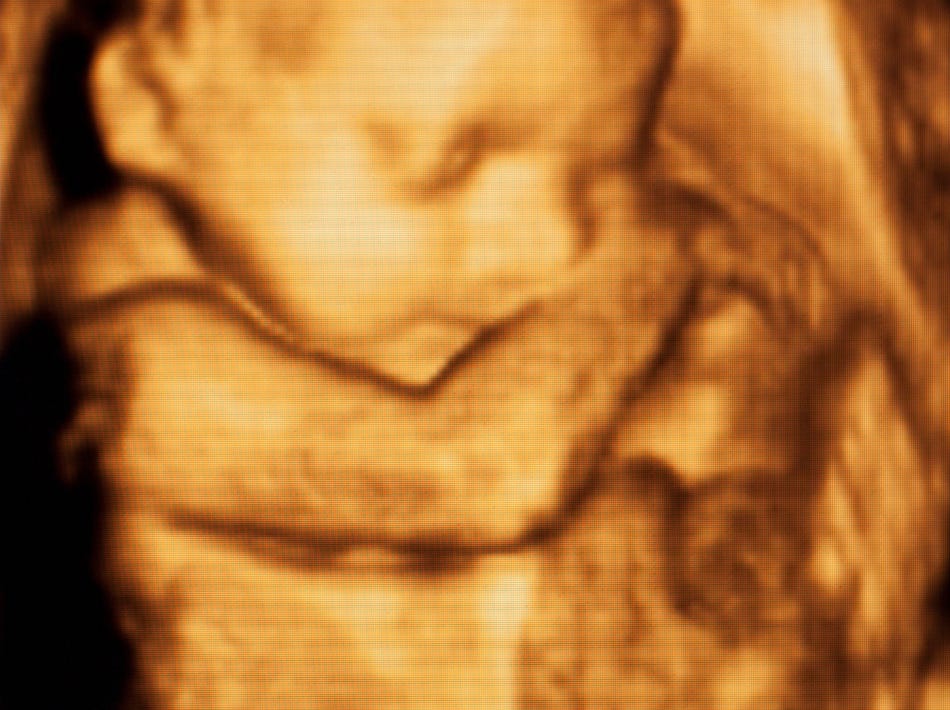

One thing Carey wrote about was the emotional impact of seeing babies about to be aborted on ultrasound screens. Carey’s abortion facility committed abortions up to twenty-four weeks, so these babies were often very developed.

In the early days at the clinic when I was scanning patients at twenty weeks, I would often see a penis or a whole foot and feel a gut punch.1

Scanning technology allows us to see very detailed images of a fetus, while private companies promise blood tests that they claim can indicate the sex as early as six weeks into a pregnancy.2

Indeed, ultrasounds, which reveal the hidden world of preborn babies in real-time, can have a powerful impact on people’s views, both about a specific pregnancy and about abortion in general.

At the Pro-Life Action League’s conference “Meet the Abortion Providers,” former abortion worker Joan Appleton told her story. Appleton was a nurse at an abortion facility. She watched an ultrasound-guided abortion in the late first or early second trimester.

I handled the ultrasound while the doctor performed the procedure, and I directed him while I was watching the screen. I saw the baby pull away. I saw the baby open his mouth. I had seen Silent Scream a number of times, but it didn’t affect me – to me it was just more pro-life propaganda.